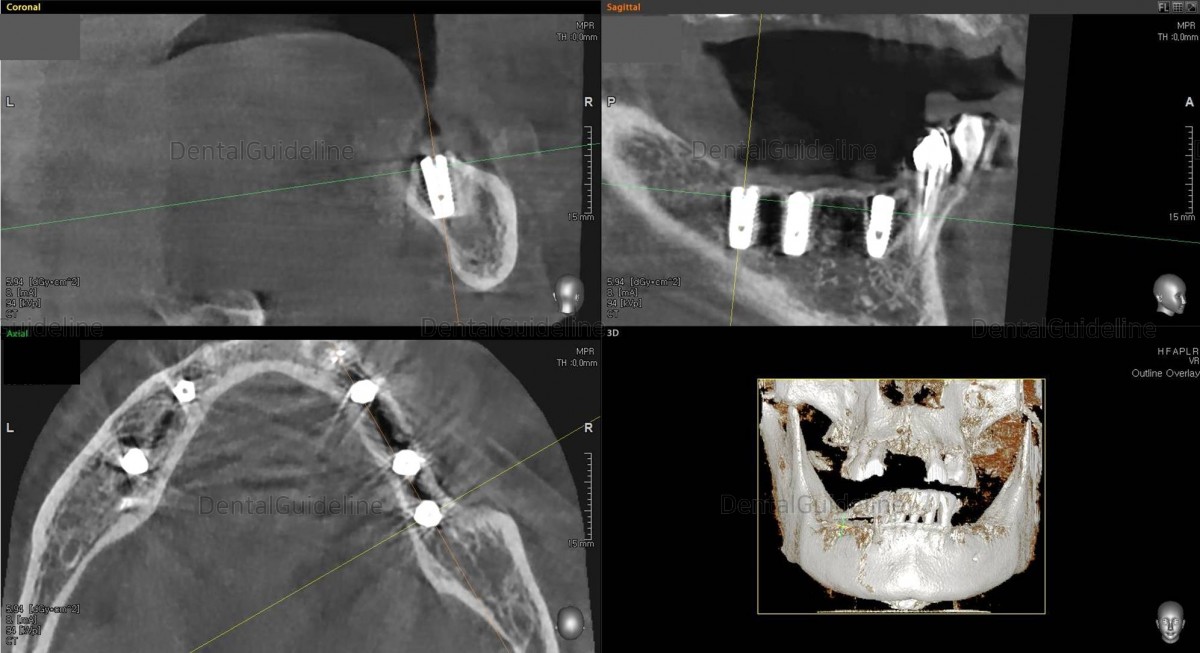

Simple

simulation of implant placement on the CBCT scan image![]()